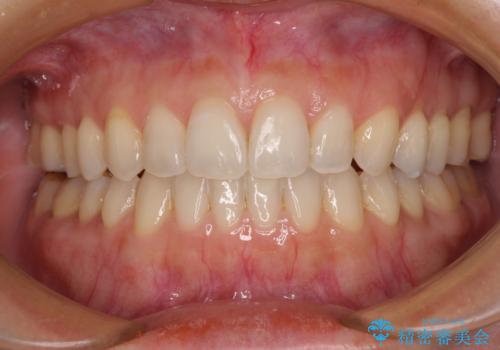

[ 前歯開咬 ] 前歯が噛んでいない マウスピース矯正治療

担当医 大元洋佑

![[ 前歯開咬 ] 前歯が噛んでいない マウスピース矯正治療の症例 治療後](https://seimitsushinbi.jp/wp/wp-content/uploads/2022/11/IMG_2488-500x350.jpg?v=1668218373)